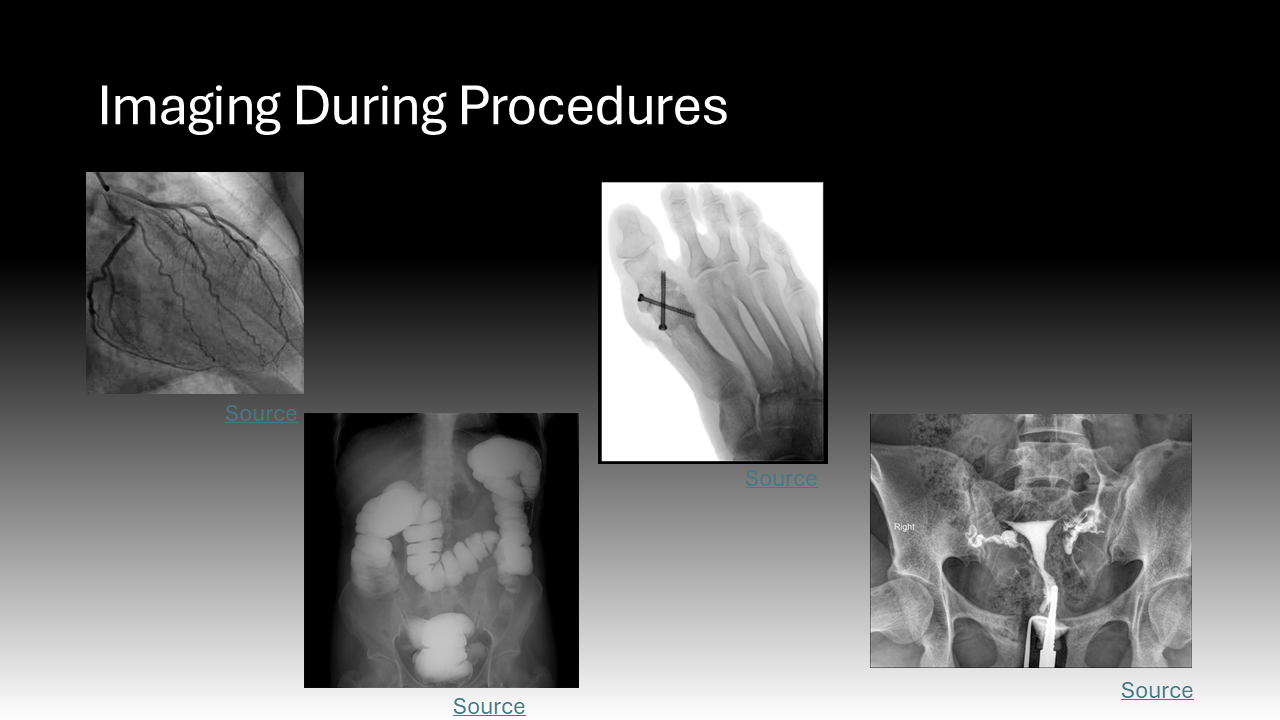

Ionizing radiation encompasses all high-energy rays that detach electrons from atoms. The body absorbs a fraction of this energy, which is disruptive at the molecular level.2 Ionizing radiation is found at low levels in the natural environment but has been employed at higher doses in medicine since the late 19th century.3 X-rays are ubiquitous in healthcare; this ionizing radiation has been the basis of two-dimensional diagnostic images and CT scans for years but is now employed during procedures.3 Cardiologists, neurosurgeons, orthopedic and vascular surgeons, and interventional radiologists all use live, continuous fluoroscopic imaging intraoperatively for “real-time feedback” during procedures.4 This technology not only allows for more accurate interventions but enables the use of minimally invasive approaches that replace open surgeries.4 In sum, the expanding use of X-ray technology in medicine, especially over the past 20 years, has led to more efficient diagnosis and treatment that is safer and more tolerable for patients.5 However, it also exposes a more diverse number of physicians to radiation and its harmful effects.5 Whereas X-rays during a diagnostic image or cancer radiation treatment are delivered to a physically isolated patient, physicians must be in close proximity to patients and radiation sources to perform procedures.5 This creates the current dilemma where healthcare providers now comprise the largest group of workers exposed to radiation in the world.5